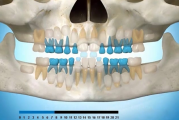

) Röntgenülesvõte. Ülemise esimese jäävmolaari lõikumine on takistatud 2. piimamolaari tõttu

Esimese jäävmolaari ektoopiline lõikumine